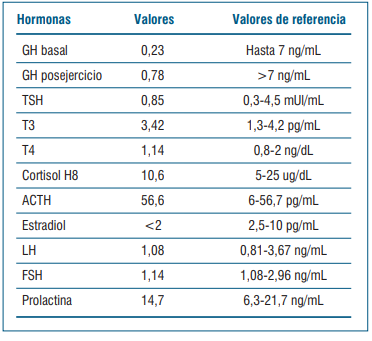

Se realiza dosificación de hormonas evidenciando una respuesta insuficiente de la GH al ejercicio y gonadotrofinas en valores prepuberales (tabla 1). El cortisol basal está en zona gris (entre 3-15 mcg/dl). Se solicitó test de estímulo con hormona adrenocorticotrópica (ACTH) para valorar insuficiencia suprarrenal (cortisol posestímulo de ACTH <18 mcg/dl), que no se realizó. En la evolución se revaloró cortisol y fue suficiente (≥15 mcg/dl).

El diagnóstico de déficit de GH se realiza por hipocrecimiento, edad ósea retrasada acorde con 8 años y con test estímulo de GH al ejercicio insuficiente. Dado que presenta alteraciones en la neuroimagen, no fueron necesarios otros test de estímulo para el diagnóstico.

No presenta clínica de déficit de hormona antidiurética, presenta ionograma y densidad urinaria sin alteraciones. No alteración de otros ejes hipofisarios (tabla 2).